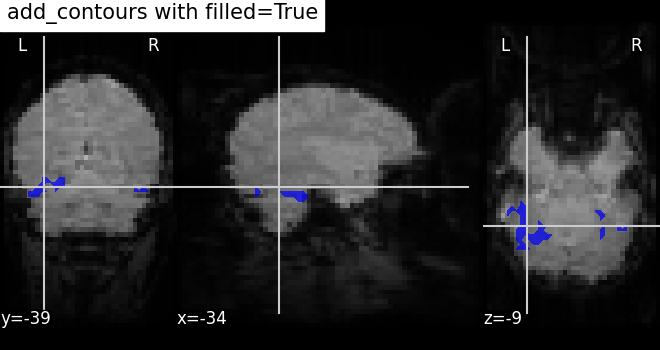

7.4. Adding overlays, edges, contours, contour fillings, markers, scale bar¶

To add overlays, contours, or edges, use the return value of the plotting

functions. Indeed, these return a display object, such as the

nilearn.plotting.displays.OrthoSlicer. This object represents the

plot, and has methods to add overlays, contours or edge maps:

display = plotting.plot_epi(...)